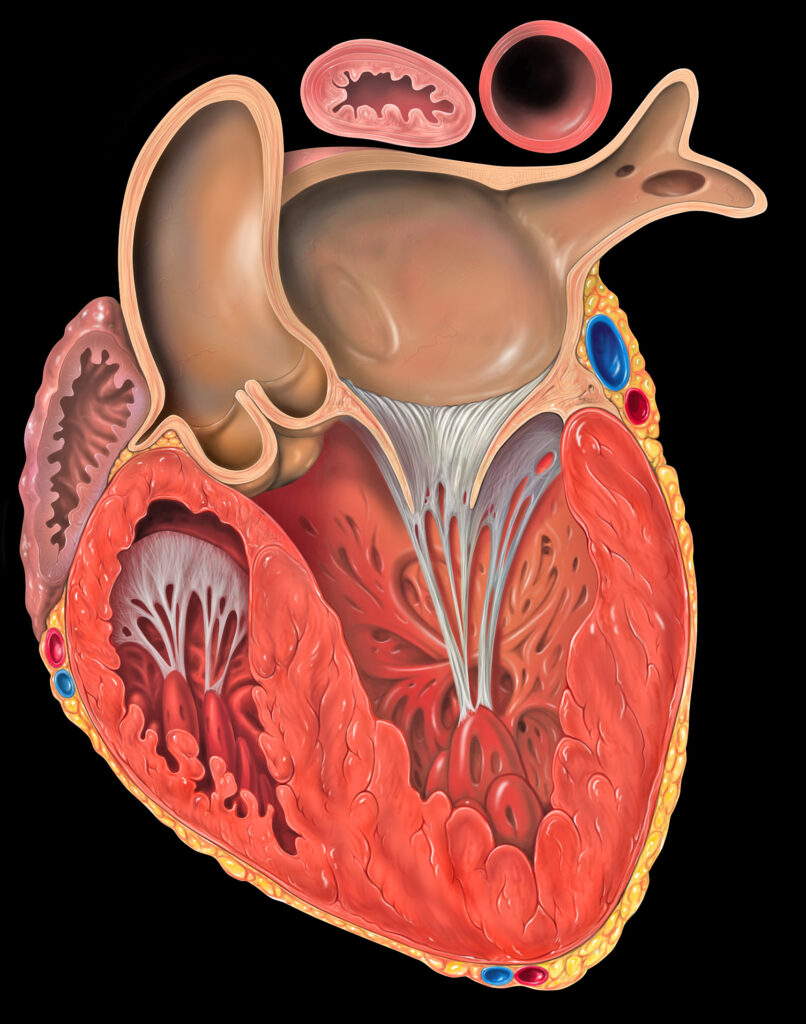

Las cuatro cámaras del corazón, las aurículas y los ventrículos, tienen diferentes características musculares que les permiten realizar esta tarea de manera eficiente.

Las aurículas son las dos cámaras superiores del corazón y su función principal es recibir la sangre de las venas que llegan al corazón. La aurícula derecha recibe la sangre pobre en oxígeno del cuerpo a través de la vena cava superior e inferior, mientras que la aurícula izquierda recibe la sangre rica en oxígeno de los pulmones a través de las venas pulmonares. Debido a que su función principal es recibir la sangre, las paredes de las aurículas son delgadas y no necesitan ser tan musculosas como las paredes de los ventrículos. Esto permite que las aurículas puedan dilatarse y expandirse con facilidad para recibir la sangre de manera eficiente.

Los ventrículos, por otro lado, son las dos cámaras inferiores del corazón y su función principal es bombear la sangre hacia las arterias. El ventrículo derecho bombea la sangre pobre en oxígeno hacia los pulmones a través de la arteria pulmonar, mientras que el ventrículo izquierdo bombea la sangre rica en oxígeno hacia el resto del cuerpo a través de la arteria aorta. Debido a que su función principal es bombear la sangre, las paredes de los ventrículos son gruesas y musculosas. Estas paredes musculares están diseñadas para realizar contracciones fuertes y rítmicas, lo que les permite bombear la sangre a través del sistema circulatorio con la fuerza necesaria.